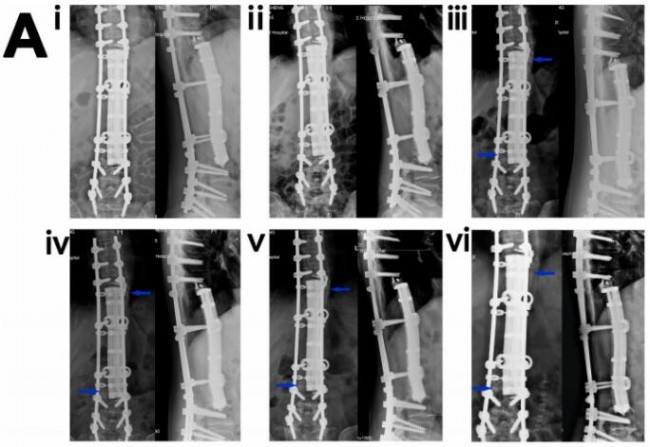

图4.3D打印多孔Ti6Al4V内植物重建脊柱骨缺损(病例1)。(A) (i-vi)术后1个月(i)、3个月(ii)、7(个月iii)、12个月(iv)、24个月(v)和32(vi)个月的“内植物-骨”X线图像。蓝色箭头表示内植物与骨界面或内植物外表面新生骨。(B)术后3个月(i)、7个月(ii)、12个月(iii)、28个月(ⅳ)、32个月(v)和36个月(vi)的CT图像。蓝色箭头表示种植体-骨界面或种植体外表面新形成的骨。